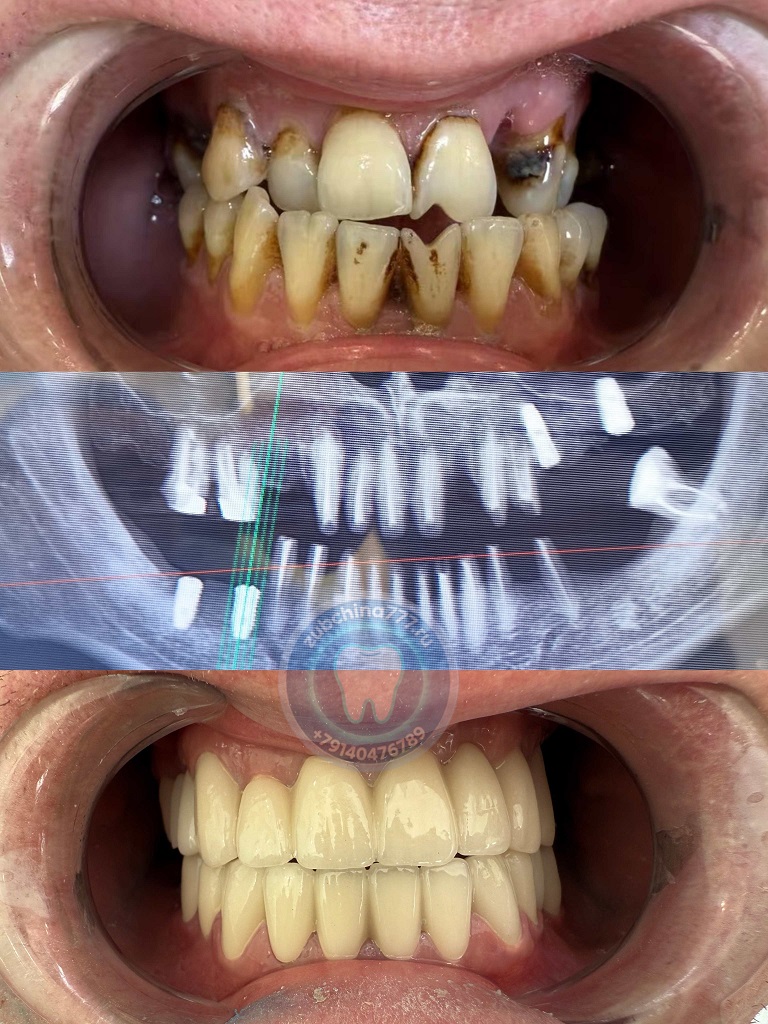

Фотографии пациентов ДО и ПОСЛЕ лечения и протезирования зубов в Хэйхэ